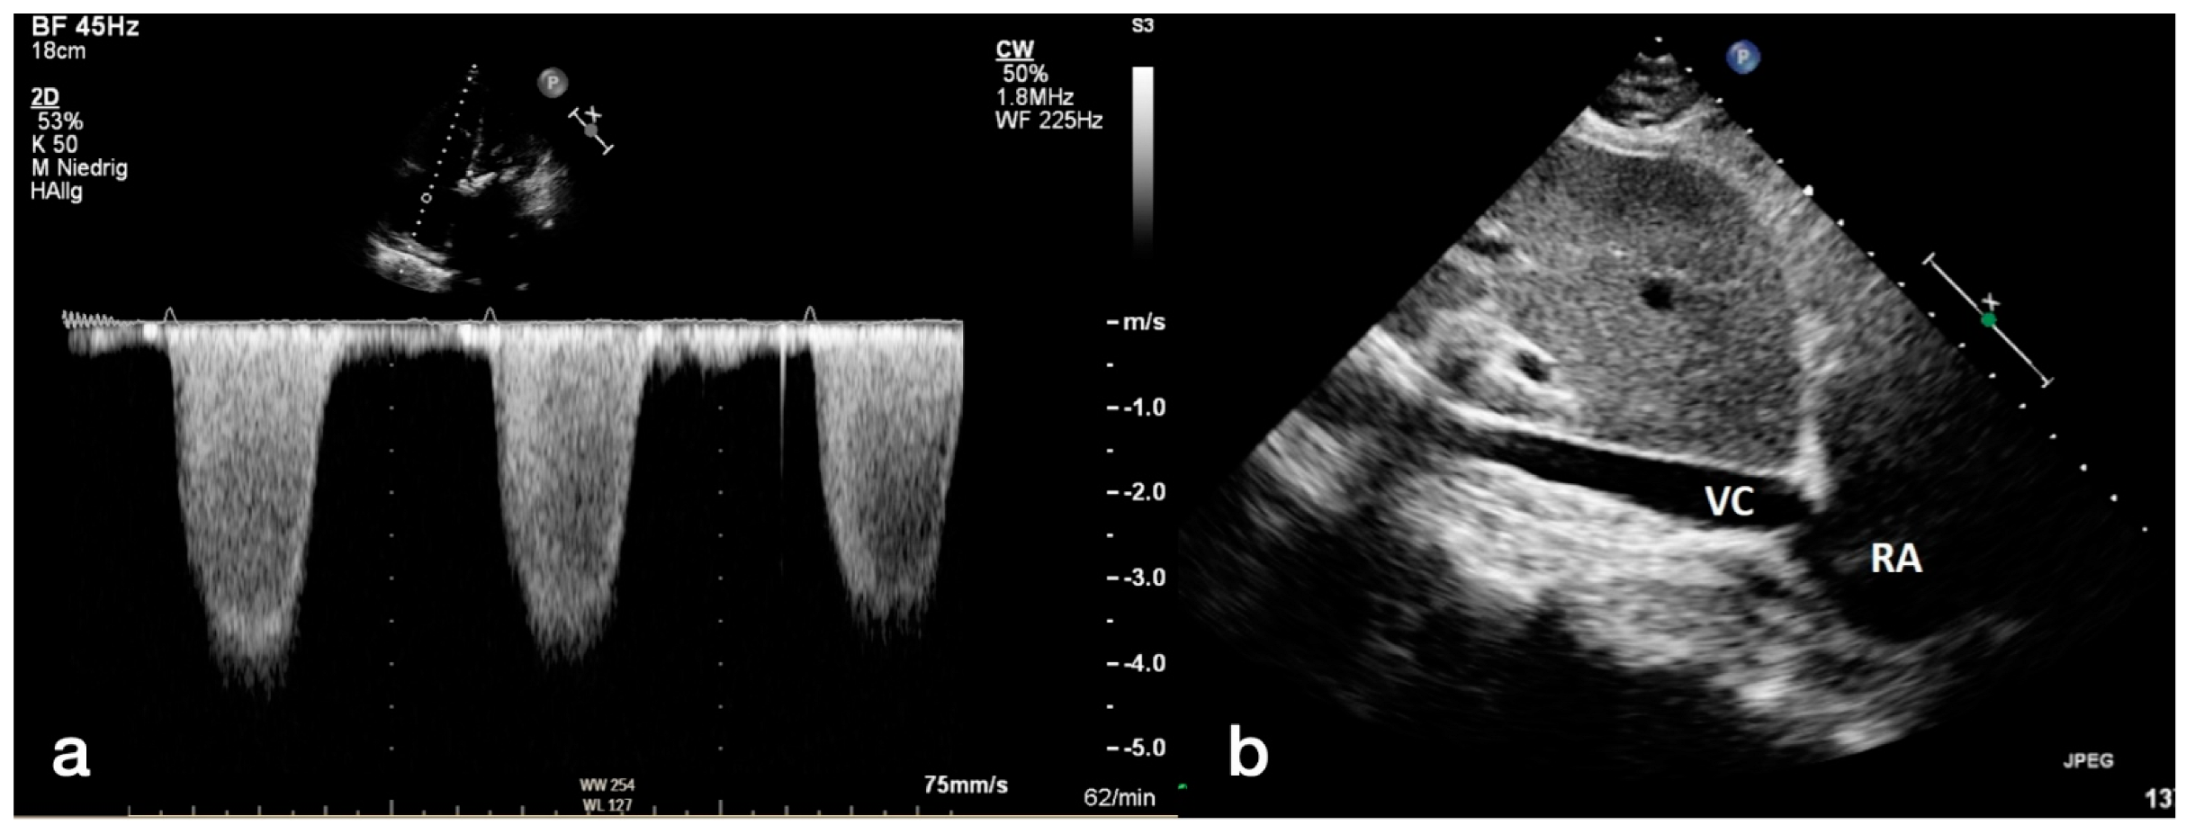

2.2. Transthoracic Echocardiography

2.3. CTA Protocol and Measurement of Diameters for PH Assessment

- The widest short-axis diameter of the main pulmonary artery (PA) within 3 cm of the bifurcation of the pulmonary trunk.

- The widest short-axis diameter of the ascending aorta (AA) at the level of the bifurcation of the pulmonary trunk.

- The widest short-axis diameter of the right pulmonary artery (RPA).

- The widest short-axis diameter of the left pulmonary artery (LPA).